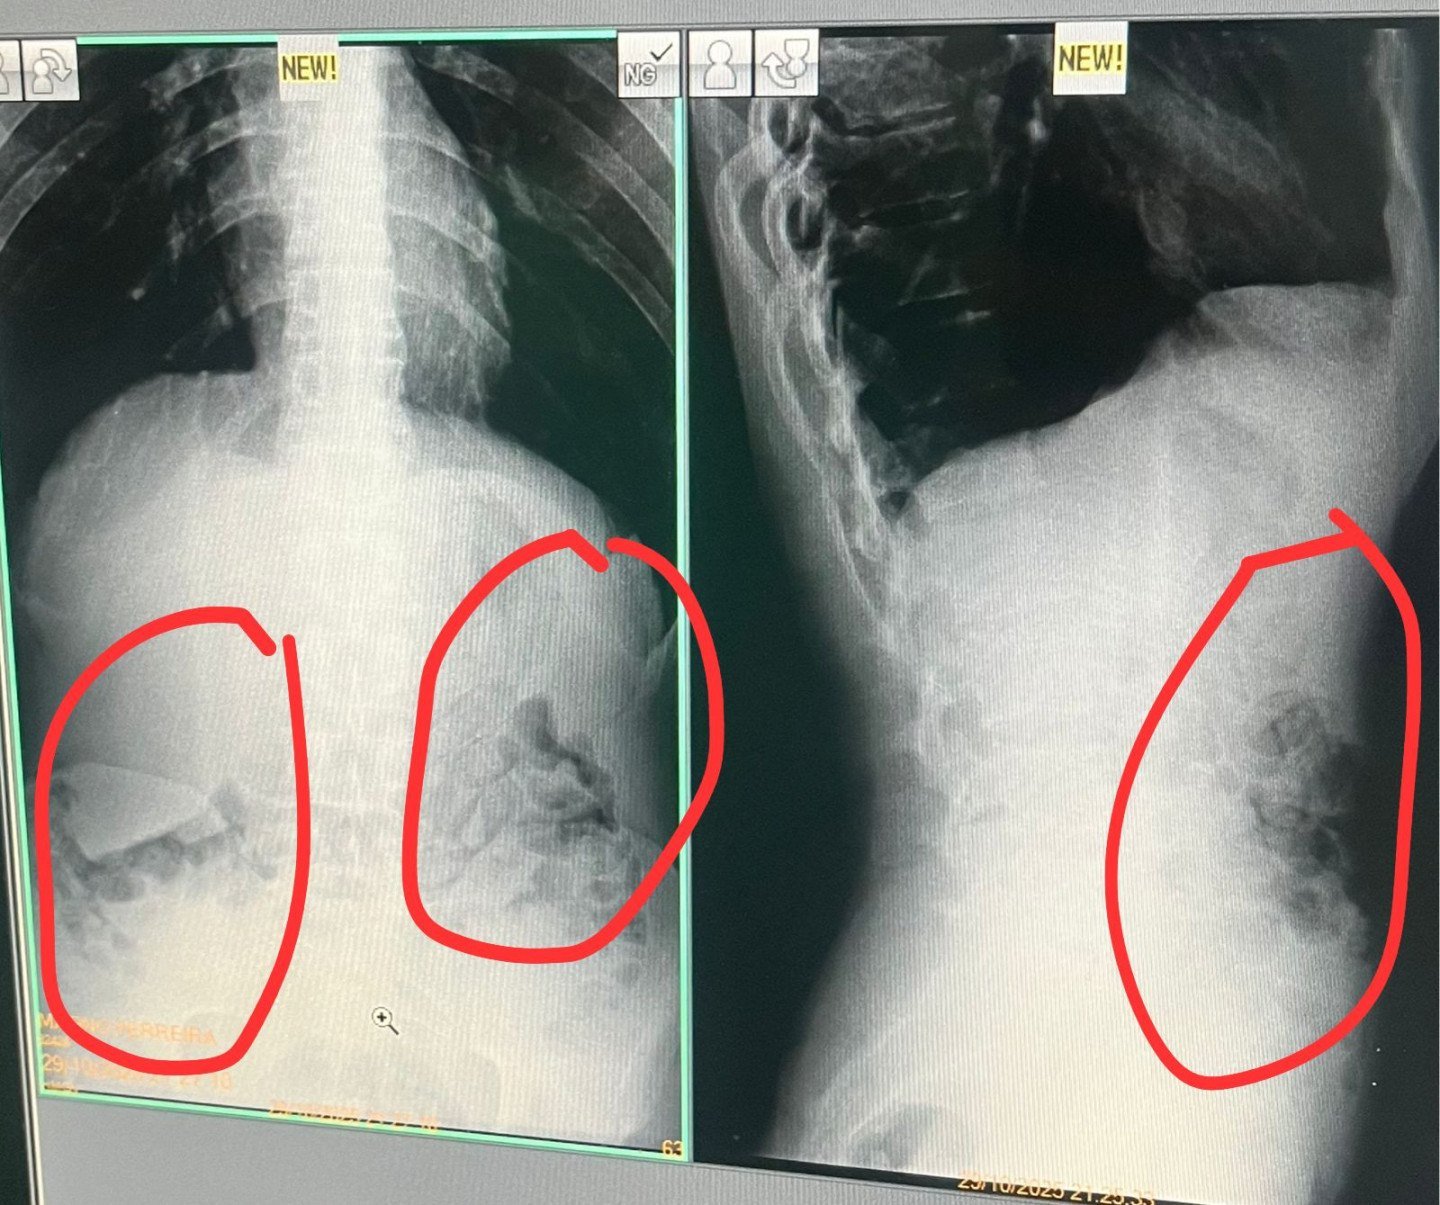

Os suspeitos foram levados ao Hospital Regional de Governador Valadares, onde passaram por exames de raio-X. O laudo confirmou que cinco deles haviam ingerido invólucros semelhantes aos encontrados no banheiro, indicando que pretendiam levar o material para dentro da unidade prisional.